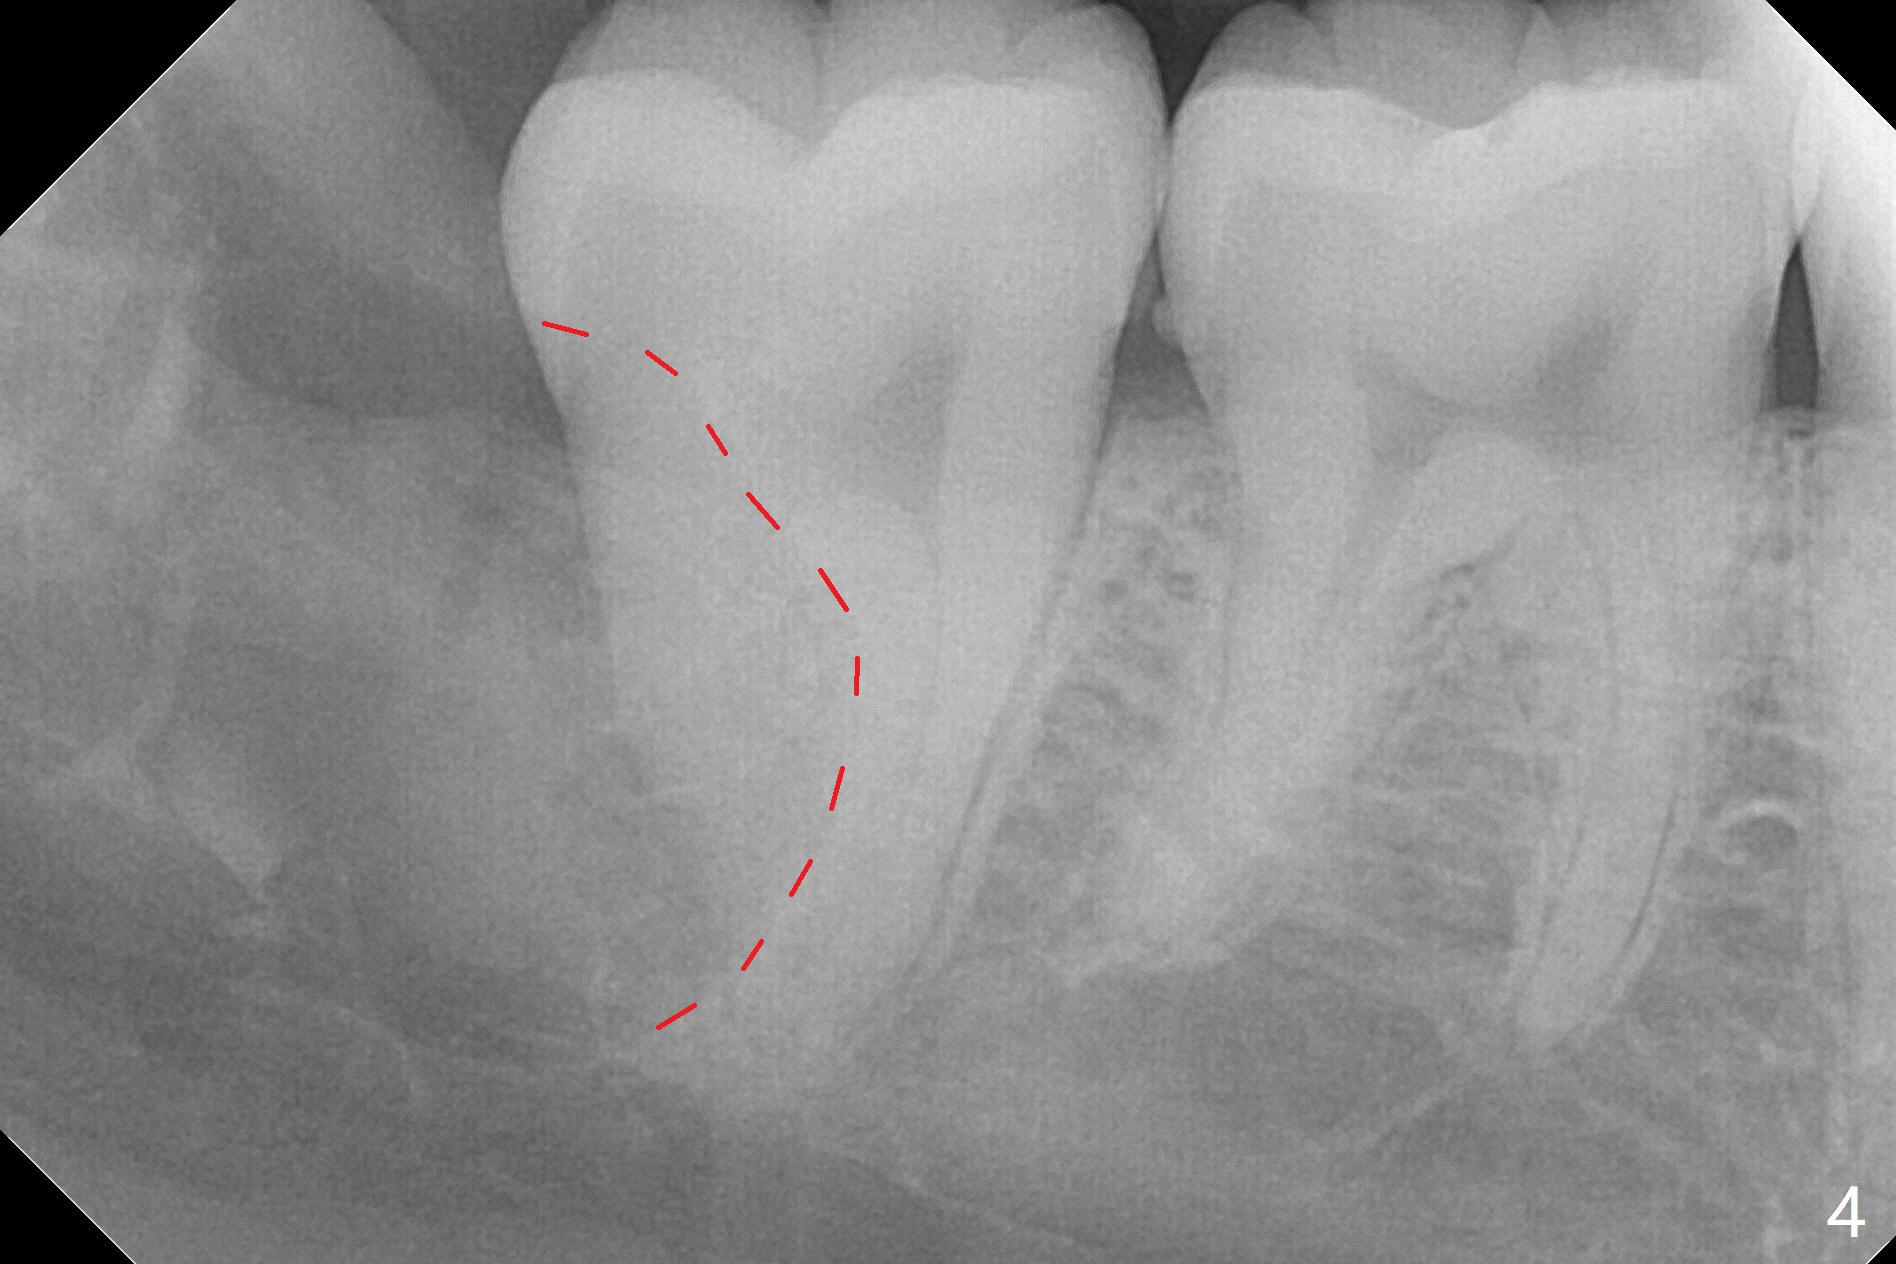

A 17-year-old man will return for extraction of 4 of the 3rd molars (Fig.1). Since the distobuccal surface of the tooth #31 may lack the bone (Fig.2 *), half of Augma will be placed in the distal portion of the sockets of #17 and 32, while allograft in the mesial one. Take PAs immediately post extraction to determine bony defects of the lower 3rd molars. Insert a piece of 2x2 gauze into the socket immediately post extraction. If hemorrhage is severe because of closeness between the mesial roots of the lower 3rd molars and the Inferior Alveolar Canal (Fig.2,3 red dashed line) after removal of the gauze, insert a half piece of Collagen Plug or more into the socket. If the latter is effective in hemostasis, Augma will be not applied, but allograft will be used, followed by Collagen Plug on the top of the allograft and sutures. Prepare both 4-0 and 5-0 ones. In fact the patient chooses to have 2 of the 3rd molars to be extracted. The extraction at #32 turns out to be extremely difficult with numerous sectioning because the crown of #32 is embedded into the distolingual surface of the fused conical roots of #31 (Fig.4,5). After insertion of a whole piece of Osteogen plug (Fig.7 O) into the root portion of the socket, Bond Apatite (1 cc) is pressed into the coronal portion of the socket (Fig.6 A). Due to oozing, the cement does not seem to be set completely. One third piece of Collagen plug is placed on the top of the cement before 4-0 Chromic gut suturing tightly. CBCT will be taken for better treatment approach prior to #17 extraction. Return to Plug Augma Xin Wei, DDS, PhD, MS 1st edition 10/06/2019, last revision 12/28/2019